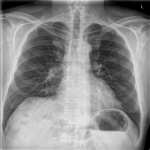

Case Report – Imaging